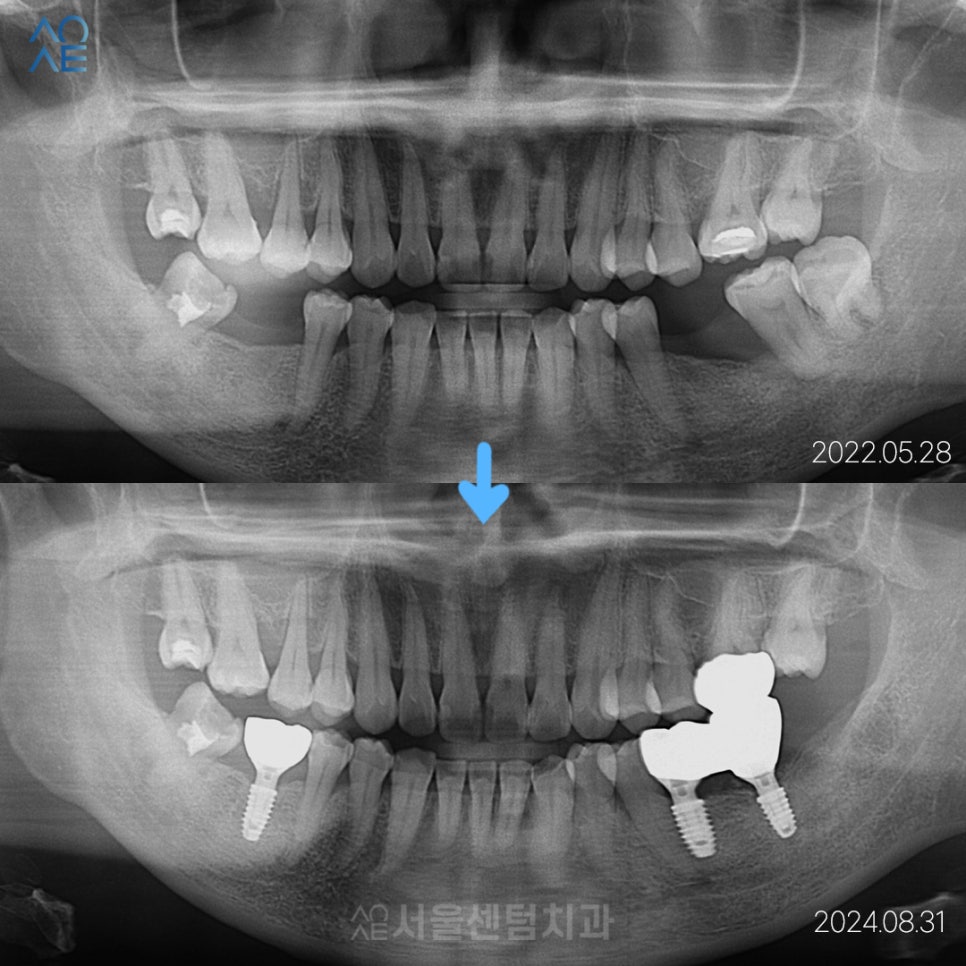

마지막으로 최종 보철물을 수복하여

최종 치료를 마무리하는 단계를 거치는데요~

임플란트 장착 후에도 1개월 체크라든가

주기적으로 오셔서 봐주시는 것이 좋습니다.

이 분의 경우엔 정말 내원을 잘 해주셔서

성공적으로 마무리 되었죠.

2022년도에 첫 인연을 맺어서

2025년 현재까지 계속 내원해주고 계십니다.